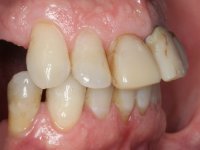

In view of the clinical situation presented, an oral rehabilitation was proposed that contemplated the antero-superior situation but also the lack of posterior teeth, seeking a more comprehensive functional and aesthetic rehabilitation. However, this proposal was not accepted, and therefore the intervention had to be restricted to the upper-antero sector. Obviously, the limitations of this intervention were explained to the patient. Thus, it was proposed to perform the endodontic treatment of tooth1.1 and to redo tooth 1.2, including: placing an intra-radicular post on 1.1 and a cast post and core in 2.1; place a provisional bridge with 3 elements with teeth 1.1 and 2.1 as abutment teeth and 2.2 as a pontic. This provisional would allow to rehabilitate the situation between the extraction of tooth 2.2 and the placement of an implant in its place. Work would be finished with 3 metal-ceramic crowns, two on teeth 1.1 and 2.1 and another on the implant placed in the site of the tooth 2.2.

Endodontic treatments were performed and a metalic non screwed intra radicular post was placed on tooth 1.1. An alginate impression was made for laboratory confection of a reinforced acrylic provisional bridge, with teeth 1.1 and 2.2 as abutments and 2.2 as a pontic. After preparation of tooth 1.1 and root preparation of 2.1, the bridge was relined in mouth with self-polymerizable acrylic using a metal post for further retaining the prepared root canal on 2.1. Tooth 2.2 was cut at the gingival level to function as support. In the same session, the impression of the root canal of the 2.1 was made for the laboratory confection of a cast post and core. A double mixture technique with plastic tutor was used after previous canal vaseline with endodontic file and cotton. The provisional bridge was provisionally cemented and the cast post and core was made in the laboratory. Cast post and core cementation was made with resin-reinforced glass ionomer cement and the provisional bridge had to be readjusted to the new situation by removing the post at the site of 2.1. After careful surgical planning, a dental implant was placed, simultaneously with extraction of the root of tooth 2.2. The provisional bridge was placed by resting on the healing screw placed in the implant. The respected osteointegration period was 12 weeks, during which the provisional bridge was relined twice. After complete maturation of hard and soft tissues, definitive impressions were made. The gingival retraction technique was applied with an impregnated retraction cord and impression was performed using double mixture, open tray impression technique. A custom precious metal abutment implant was prepared in the lab, along with 3 metal caps to be used as infrastructures for the metal ceramic crowns. Particular care was taken in the confection of the cervical finishing line of the implant abutment, in order to follow the soft tissues emergence profile. Proof of infrastructures was done in the mouth being evaluated clinically and imagiologically. Collection of color information was done by the ceramist at the office. Ceramic was applied in the laboratory and the finished work was placed in the mouth after approval by the patient. Definitive cementation was made with resin-reinforced glass ionomer cement, and the first crown to be cemented was that of the implant, to facilitate removal of the excess.